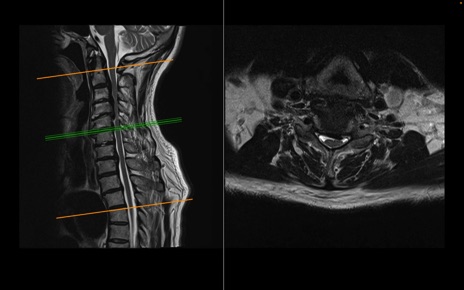

頚椎MRI

T2WI(横断像)

T2WI(矢状断像)